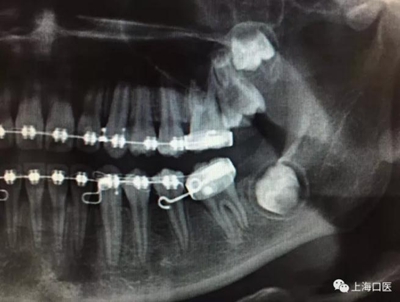

這是上海武廣增正畸工作室接診的一例非常規(guī)拔牙矯治病例,患者女性,初診年齡14歲。LL6殘冠拔除。LL7近中平移取代LL6,我們上傳了該患者一組下頜磨牙近中平移連續(xù)矯治過程的正畸X線片,與正畸界朋友分享。